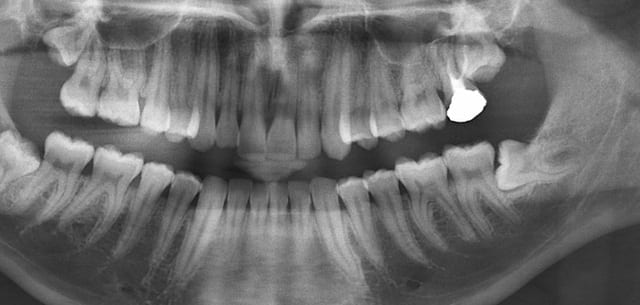

pour extraction de 48.

Effectivement les apex dépassent le bord inf. de la mandibule.

Merci. Je l'ai adressée hier au service de chirurgie maxillo-faciale universitaire de Bâle.C'est plus proche pour la patiente.Il y a non seulement un risque de fracture mais également un risque de lésion du NAI.Il faudra aussi faire une histologie de la lésion "Kystique".Je précise par ailleur qu'il n'y a aucune symptomatologie et 47 est vivante.

ca doit etre un kyste dentigere

Un autre risque potentiel dans cette chir qui n'a pas été évoqué me semble-t-il est la lésion de l'artère faciale.

elle chemine dans la région submandibulaire en faisant une boucle puis revient ensuite vers l'avant pour passer sous le rebord mandibulaire à la hauteur de la 6 du bas environ.

Par ailleurs si la patiente repousse à chaque fois l'extraction, on n'a qu'à lui proposer l'alternative d'une dcompression avec mise en place d'un cathéter et puis on surveille tout simplement.

Avec un peu de chance la dent va remonter au fur et à mesure que le kyste se resorbe.